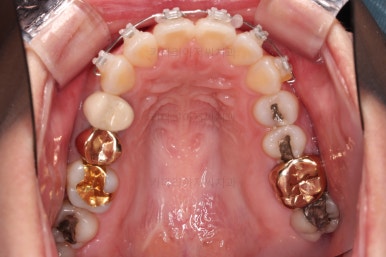

사용한 장치 : 자가결찰 세라믹(엠파워 클리어, Empower clear) + 미니튜브 + 미니스크류

웃을 때 모습에서 앞니가 조금 삐뚤어 미적으로 좋지 못하고, 특히나 대문니가 더 튀어나와 강조되어 보이고 유달리 커보이는 효과까지 주네요.

어금니의 맞물린은 100점은 아니지만 생활하기에 크게 나빠보이지 않고요.

특히 임플란트도 있는 상황이었기 때문에 굳이 어금니까지 교정할 필요는 없어보였어요.

앞니 부분교정으로 치료계획을 세웠는데 다른 분들에 비해 난이도가 높은 치료가 예상되었던 이유는 우측 상단의 사진에 선 그어놓은 부분을 보시면 어금니에 비해 아래앞니가 약간 솟구쳐 높이가 맞지 않다는 점이었어요.

이 부분을 개선하기 위해 일반적인 부분교정 외에 추가적인 장치가 필요했었습니다.